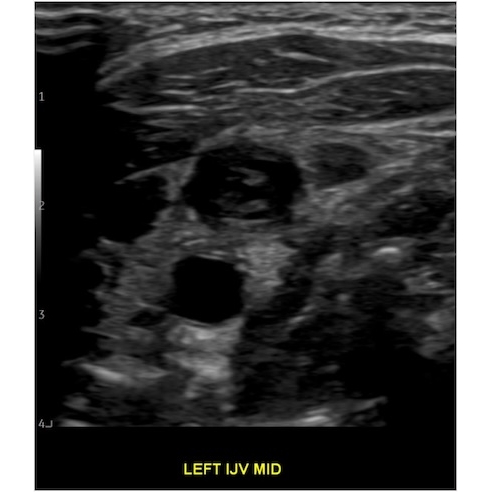

Given her significant neck swelling, ED providers ordered venous doppler ultrasound of the upper extremities.

Venous Doppler of the Upper Extremity bilateral: Occlusive thrombus within the left internal jugular vein measuring approximately 3.1 cm length. Case Photo #10 , Case Photo #2 and Case Photo #3